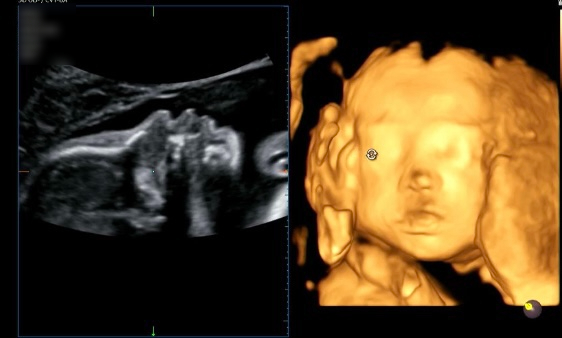

임신 7개월 24 25 26주 임산부 일상 | 강남차병원 임당검사| 열달후에 | 입체초음파 성공| 밤부베베 손수건 세탁팁

임신 7개월 24 25 26주 임산부 일상 | 강남차병원 임당검사| 열달후에 | 입체초음파 성공| 밤부베베 손수건...